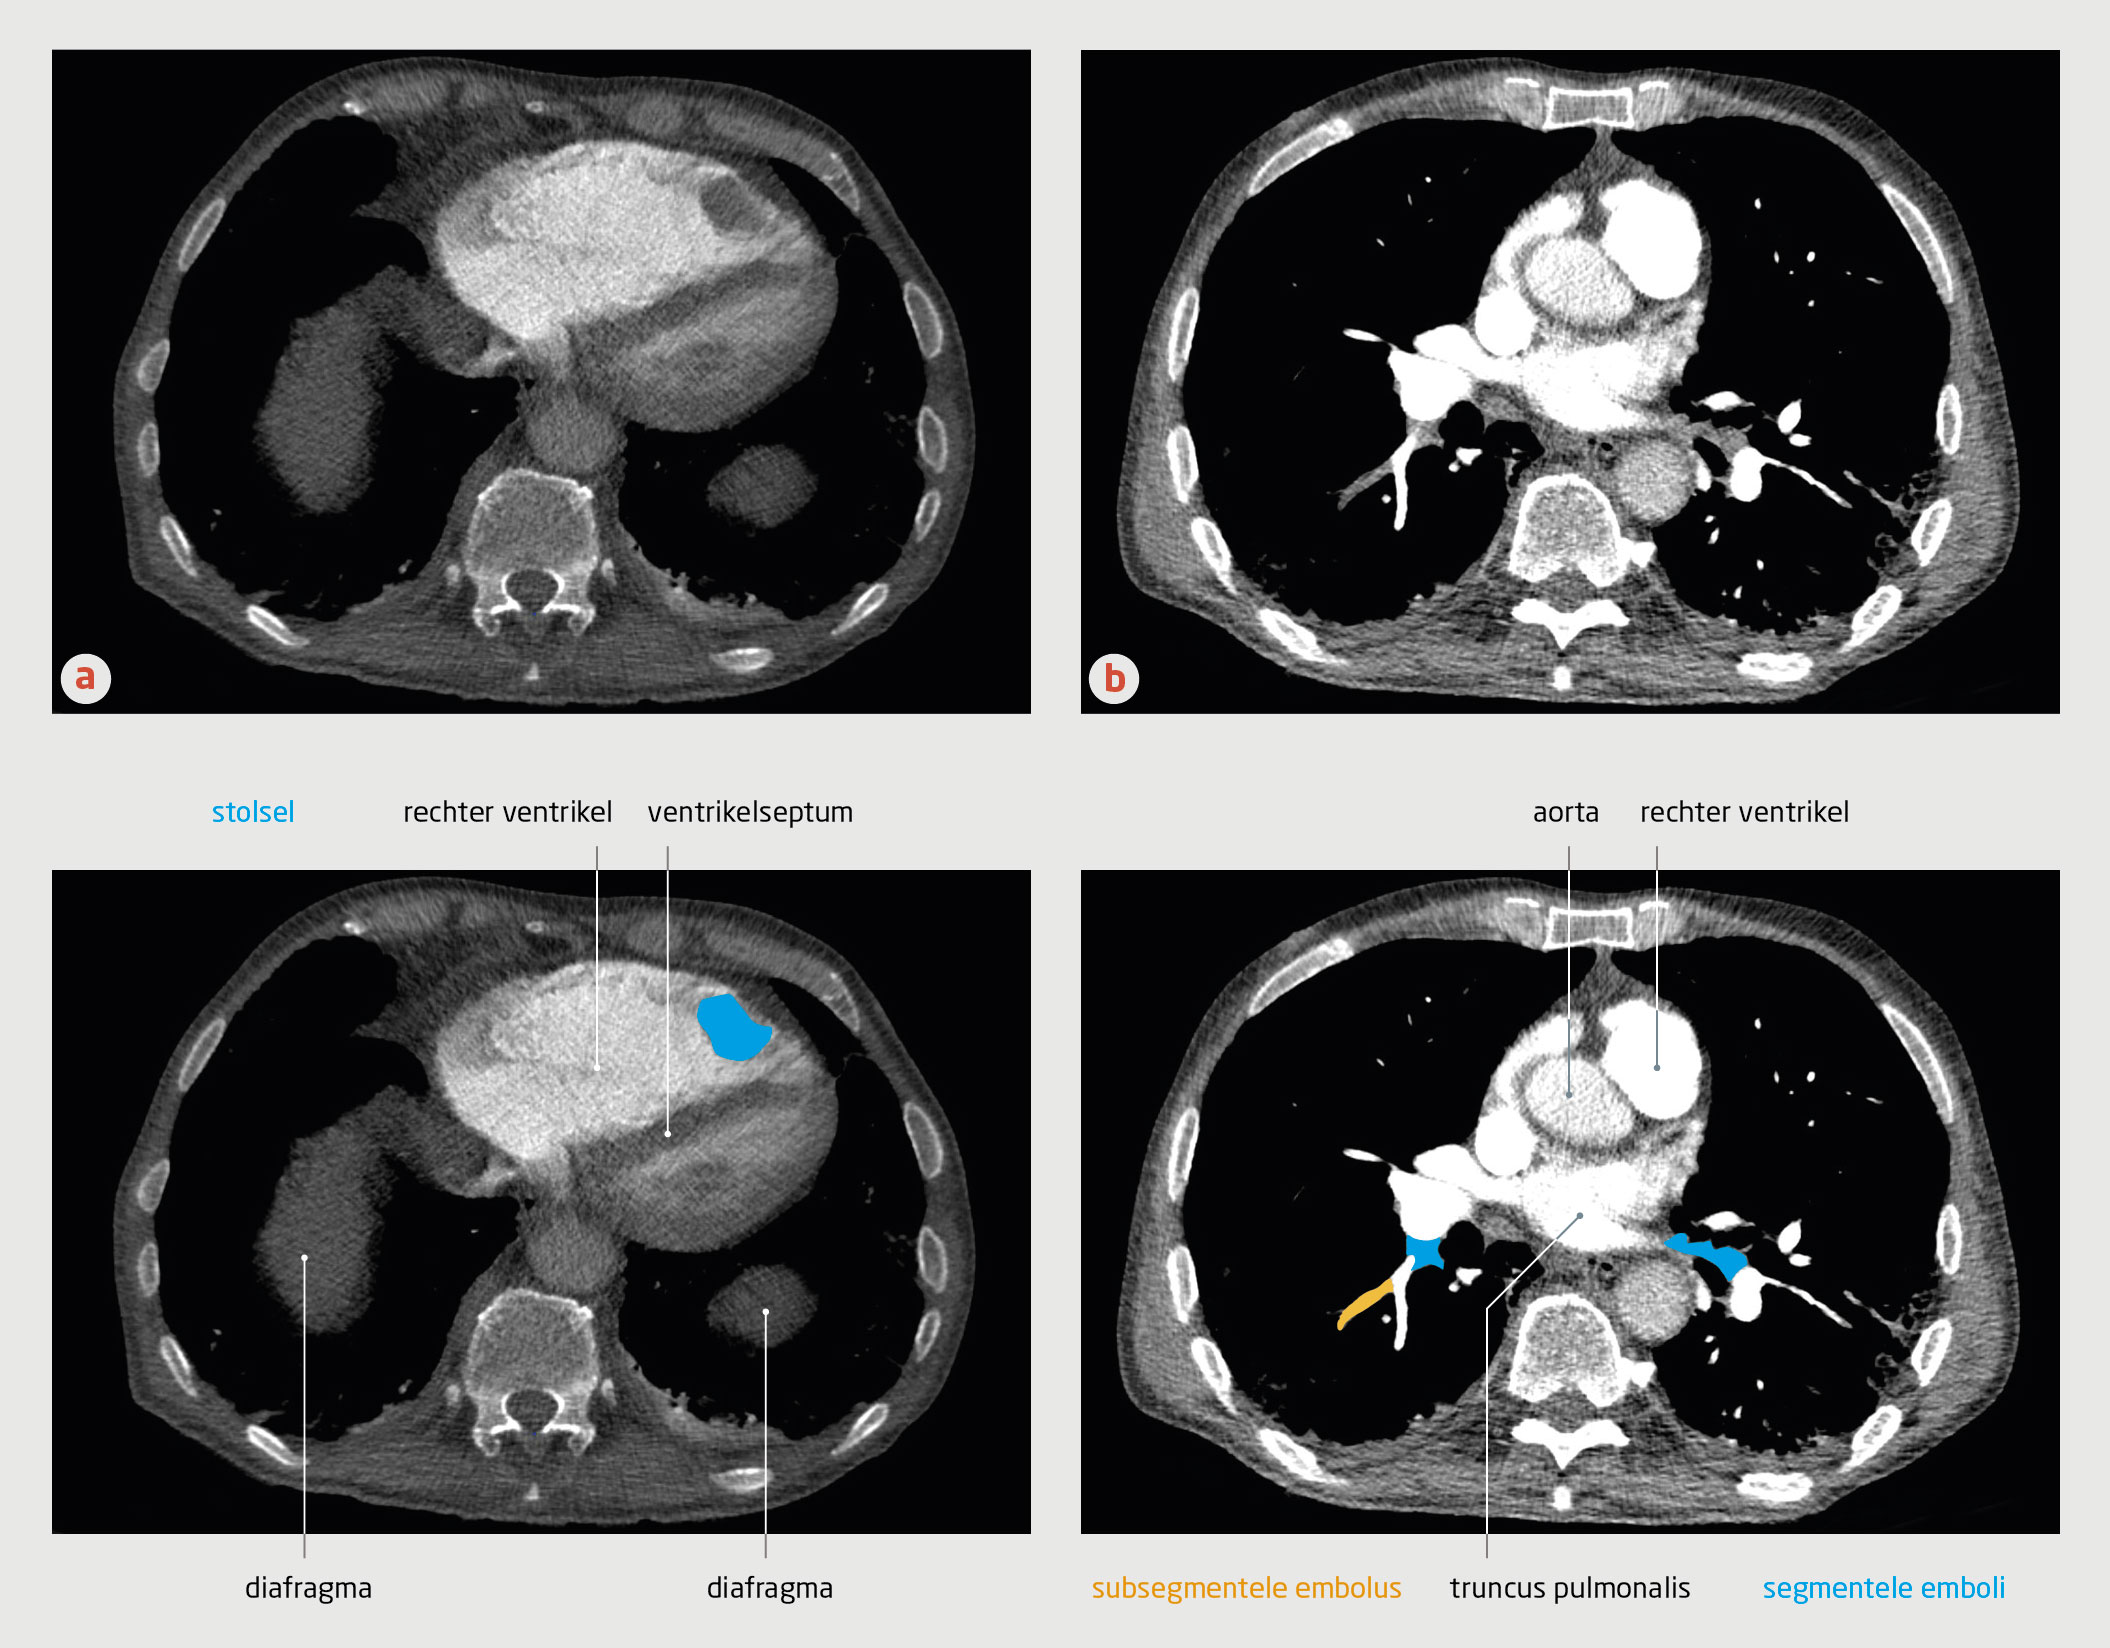

Figuur 3

CT-angiografie van de thorax van patiënt C

Figuur 3 | CT-angiografie van de thorax van patiënt C

CT-angiografie met contrast van patiënt C (transversale coupe). (a) In de rechter ventrikel bevindt zich een stolsel. De rechter ventrikel is vergroot en er is sprake van septumdeviatie, passend bij overbelasting van de rechter ventrikel. (b) Bij deze patiënt was sprake van zowel segmentele als subsegmentele longembolieën.

Gezien dit klinische beeld, de D-dimeerwaarde van 3,3 mg/l en een sterke verdenking op longembolie werd op grond van het YEARS-algoritme (afkapwaarde voor D-dimeer: 0,5 mg/l) een CT-A verricht. Deze liet multipele segmentele en subsegmentele longembolieën zien, alsmede een stolsel in de apex van de rechterventrikel met een diameter van 3 cm (figuur 3).

In de verklarende tekening bij figuur 3b van dit artikel zijn enkele structuren onjuist aangegeven. In het onderschrift bij deze figuur staat ten onrechte dat in figuur 3b segmentele embolieën zichtbaar zijn. Hieronder staat de juiste figuur met het correcte onderschrift.